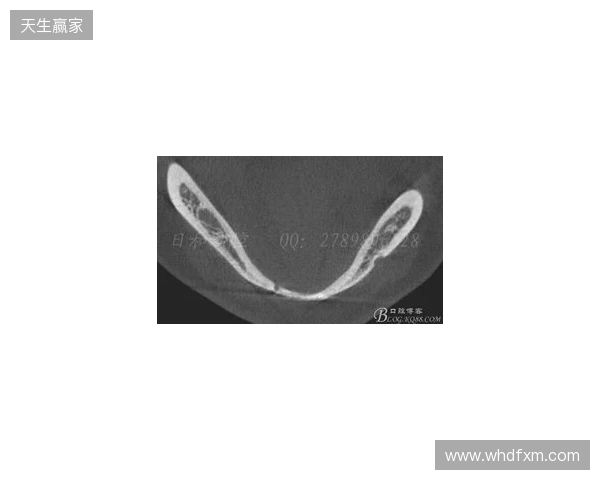

在2026赛季中超联赛首轮的比赛中,韦林顿·席尔瓦遭遇了严重的伤病,导致他上唇部受伤,并且出现了牙齿和牙槽骨的损伤。根据华西口腔医院的诊断,席尔瓦的伤情包括上唇部贯通伤、两颗牙齿半脱位以及上颌前牙区牙槽骨骨折。此事件不仅对球员本人构成了巨大的身体挑战,也给球队带来了不小的影响。伤病的发生让人揪心,球迷们纷纷为席尔瓦送上祝福,希望zbo1919他能尽快康复,重返赛场。

根据医院的检查结果,韦林顿·席尔瓦的上唇部受伤程度较为严重,属于贯通伤,已经进行了清创缝合。这种类型的伤势不仅影响外观,还可能对球员的饮食和发声造成影响。更为严重的是,他的上颌前牙区还出现了骨折,意味着席尔瓦在恢复期间将面临长时间的治疗和康复过程。

球员的第11和第21牙出现了半脱位的情况,这可能会导致他在恢复后需要进行进一步的牙科治疗,甚至有可能影响到他今后的职业生涯。医生表示,虽然通过手术和治疗可以恢复,但心理层面的恢复同样重要。